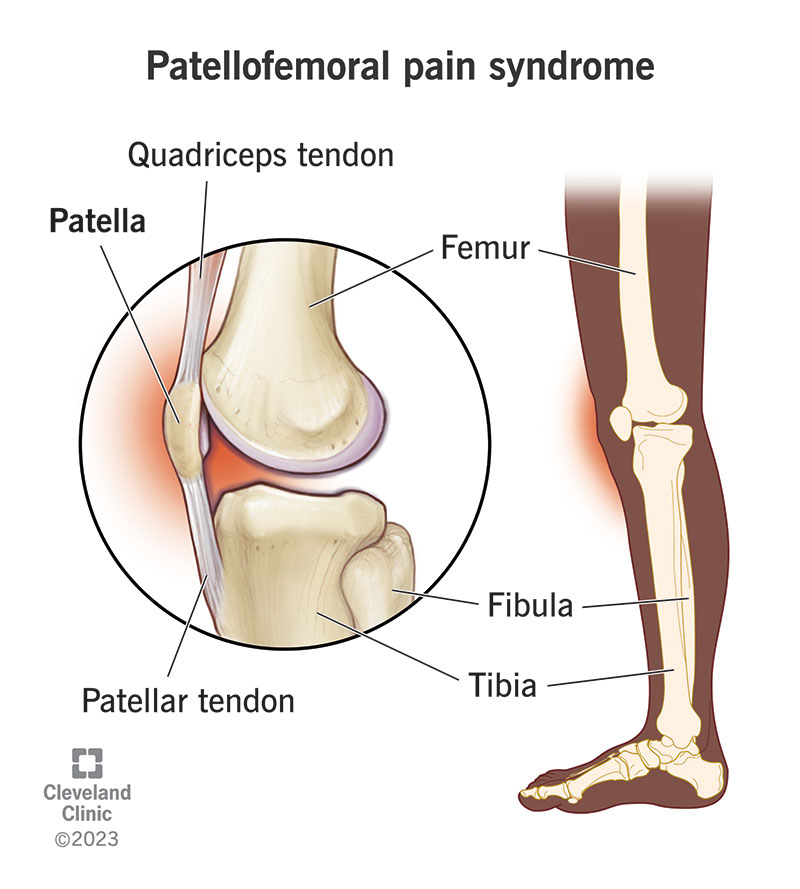

Patella Kneecap Anatomy and Function discount, Knee Bones Anatomy Function Injuries Knee Pain Explained discount, The knee Anatomy injuries treatment and rehabilitation discount, Knee Joint Function Anatomy discount, Where or Where Has My Patella Gone Direct Orthopedic Care discount, Guide to Knee Joint Anatomy Sports health discount, Patellar Fractures Broken Kneecap OrthoInfo AAOS discount, The Knee UT Health San Antonio discount, Normal Anatomy of the Knee Joint Middletown Knee Treatment Old discount, Knee Joint Anatomy Structure Function Injuries Knee Pain Exp discount, Your Knee Just Knees discount, Knee Joint Anatomy and Arthritis SHELBOURNE KNEE CENTER discount, Knee Pain Causes Treatment discount, Detailed Anatomy of the Knee Joint discount, Knee Anatomy and Function Restoration Orthopaedics Restoration discount, Knee Joint Overview Cioffredi Associates discount, Knee Pain What causes it what to do if I have it and how to discount, Patella Wikipedia discount, Kneecap Dislocation discount, Physiotherapy in Calgary for Knee Pain Bipartite Patella discount, Knee pain Wikipedia discount, Knee Trauma Fractures of the Patella Tibial Plateau and Distal discount, The Knee Joint Articulations Movements Injuries TeachMeAnatomy discount, The Kneecap Patella and Knee Joint Saint Luke s Health System discount, Knee Joint Anatomy Structure Function Injuries Knee Pain Exp discount, Knee Anatomy Sweep discount, Matthew Boyle Orthopaedic Surgeon Knee Anatomy Knee discount, Knee replacement Understanding your knee discount, Anatomy of the Knee Worcestershire Knee and Hip Clinic discount, Patellofemoral Pain Syndrome My Family Physio discount, Patellofemoral Pain Syndrome PFPS Symptoms Treatment discount, Kneecap Fractures Patella Fractures Johns Hopkins Medicine discount, Knee anatomy including ligaments cartilage and meniscus discount, Mystery arthritis linked knee bone three times more common than discount, Knee muscle and tendon injuries Chris Bailey Orthopaedics discount.

Bones in your knee cap discount